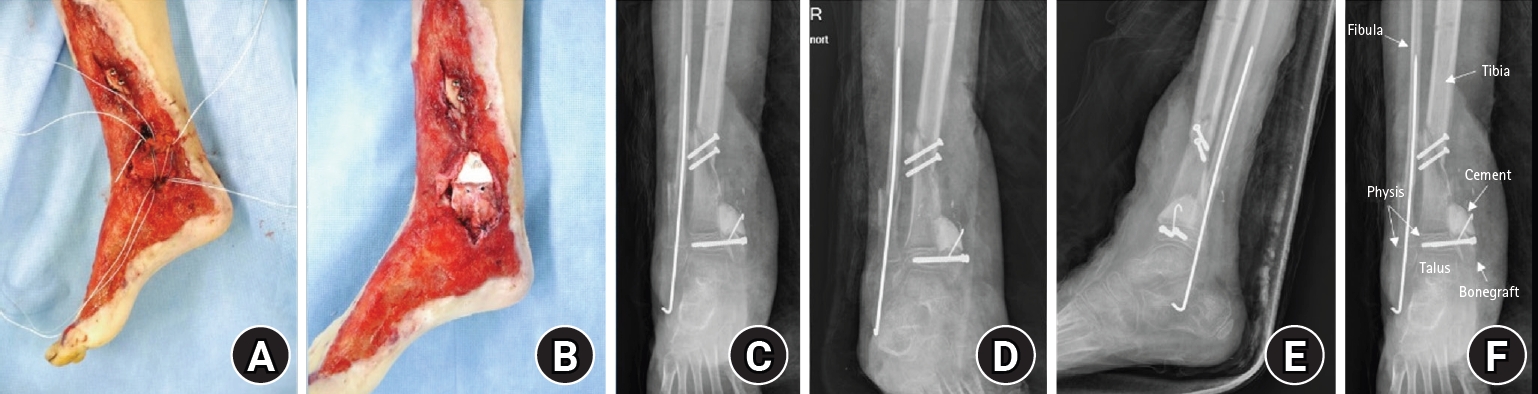

Stage 2 (definitive reconstruction; August 6, 2016)

The medial malleolar defect (2.5×2.0 cm) was reconstructed using an autologous iliac crest bone graft harvested and contoured to match the defect (Fig. 3) [4,5]. The graft was secured with internal fixation, and postoperative clinical appearance and radiographs confirmed reconstruction and stabilization (Fig. 4). To restore medial ankle stability, harvested gluteal fascia was used as a deltoid ligament substitute and fixed using suture anchors [1]. To mitigate physeal bridging in the residual void adjacent to the injured physis, a bone-cement spacer was placed [4,5]. The extensive soft-tissue defect was covered using ALT flap and skin graft, achieving stable coverage (Fig. 5) [6,7].

Fig. 3.

Autologous iliac crest bone graft. Intraoperative photograph of the harvested autologous iliac crest bone graft prepared for medial malleolus reconstruction (defect size, 2.5×2.0 cm).

Fig. 4.

Postmedial malleolus reconstruction. (A) Medial clinical photograph obtained after reconstruction of the medial malleolus using an autologous iliac crest bone graft with internal fixation. (B) Medial clinical photograph obtained after reconstruction, showing restoration of the medial malleolar contour and soft-tissue coverage. (C) Anteroposterior postoperative radiograph demonstrating reconstruction of the medial malleolus with internal fixation. (D) Mortise postoperative radiograph demonstrating reconstruction of the medial malleolus with internal fixation. (E) Lateral postoperative radiograph demonstrating reconstruction of the medial malleolus with internal fixation. (F) Anteroposterior radiograph, showing the reconstructed medial malleolus and surrounding anatomical structures.

jmt-2026-00059f4.jpg

Fig. 4. Postmedial malleolus reconstruction. (A) Medial clinical photograph obtained after reconstruction of the medial malleolus using an autologous iliac crest bone graft with internal fixation. (B) Medial clinical photograph obtained after reconstruction, showing restoration of the medial malleolar contour and soft-tissue coverage. (C) Anteroposterior postoperative radiograph demonstrating reconstruction of the medial malleolus with internal fixation. (D) Mortise postoperative radiograph demonstrating reconstruction of the medial malleolus with internal fixation. (E) Lateral postoperative radiograph demonstrating reconstruction of the medial malleolus with internal fixation. (F) Anteroposterior radiograph, showing the reconstructed medial malleolus and surrounding anatomical structures.